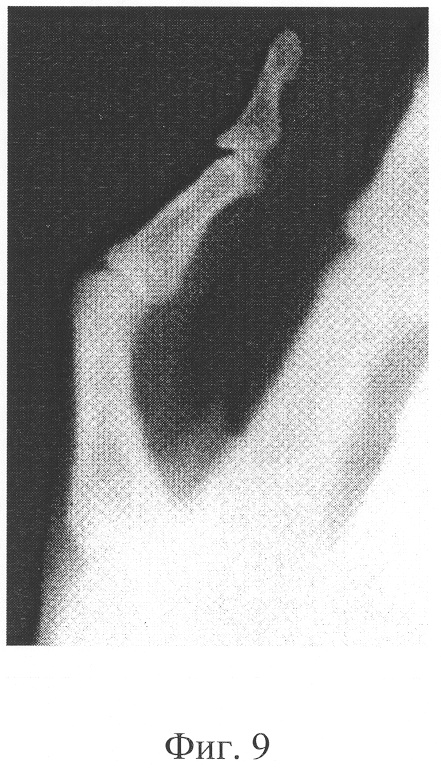

Предложение иллюстрируется чертежами, где на фиг.1 представлена фотография исходной поверхности отдельной нити графитового катода до взрыва; на фиг.2 представлена фотография поверхности отдельной нити графитового катода после 104 включений; на фиг.3 представлены осциллограммы импульсов высокого напряжения и рентгеновского излучения; на фиг.4 схематично показана рентгеновская трубка; на фиг.5 схематично показана конструкция графитового катода; на фиг.6 представлена фотография поверхности графитового катода, где видны отдельные нити; на фиг.7 представлена таблица с параметрами аппарата с заявляемой рентгеновской трубкой; на фиг.8 представлена рентгеновская интроскопия микрокалькулятора, напряжение U=37 кВ; на фиг.9 представлен рентгеновский снимок руки с дефектом сустава большого пальца, напряжение U=35 кВ; на фиг.10 представлен рентгеновский снимок биологического объекта – куриной ножки, напряжение U=40 кВ; на фиг.11 представлен рентгеновский снимок биологического объекта – внутренних органов рыбы, напряжение U=30 кВ; на фиг.12 представлен рентгеновский снимок биологического объекта – ножки цыпленка с переломами костей, напряжение U=32 кВ.

Изготовлена и испытана рентгеновская трубка с параметрами, представленными в таблице на фиг.7. Примеры рентгеновских снимков различных биологических объектов, представленных на фиг.8-12, позволяют видеть четкое изображение объектов разной оптической плотности.

При подаче на электроды трубки, а именно на анод 2 и катод 3, импульса напряжения с крутым фронтом происходит взрывообразное тепловое разрушение автоэмиссионным током микроострий, которые всегда имеются на эмиттерах. После окончания импульса напряжения на поверхности катода 3, практически мгновенно, застывает микроструктура, повторное приложение к которой достаточного электрического поля приводит к повторному акту взрывной электронной эмиссии с параметрами, полностью воспроизводящими предшествующий эмиссионный импульс. Как пример на фиг.9 представлен рентгеновский снимок руки с дефектом сустава большого пальца, полученный при подаче 40 импульсов длительностью 20 нс, напряжением U=35 кВ.